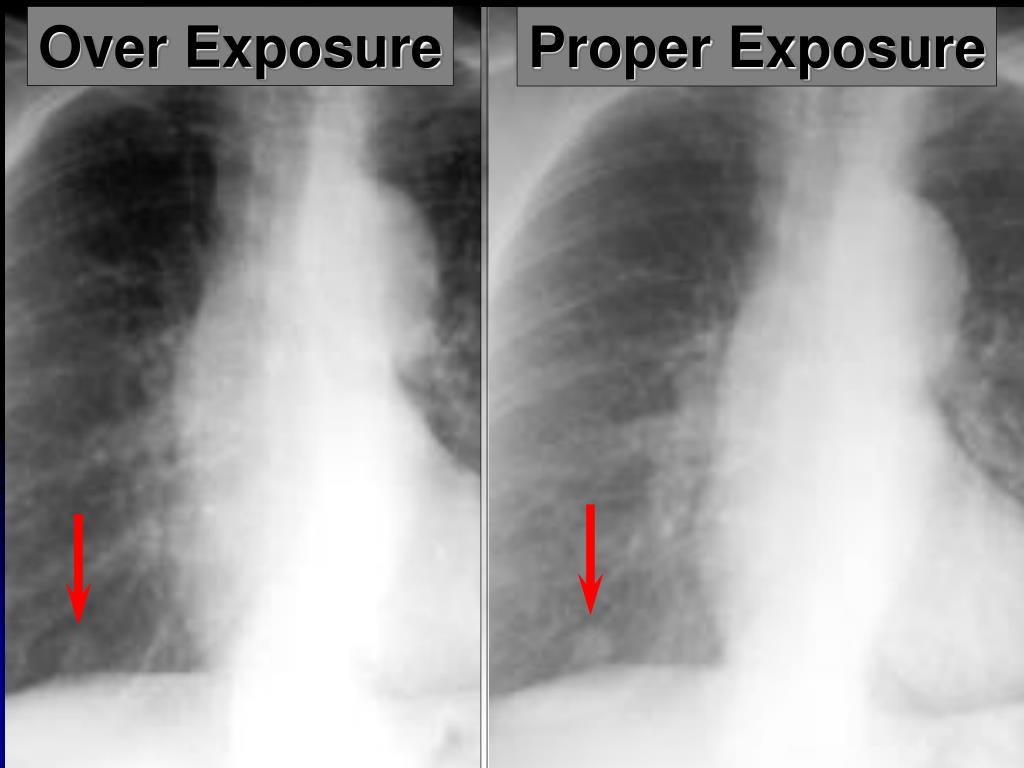

11. Proper Exposure Over Exposure

5. Approach to the CXR: Technical Aspects • Projection – PA or AP • Position – Upright or Supine (Supine folks are sick) • Inspiratory effort • 9-10 posterior ribs • Penetration • thoracic intervertebral disc space just visible • Positioning/rotation • medial clavicle heads equidistant to spinous process